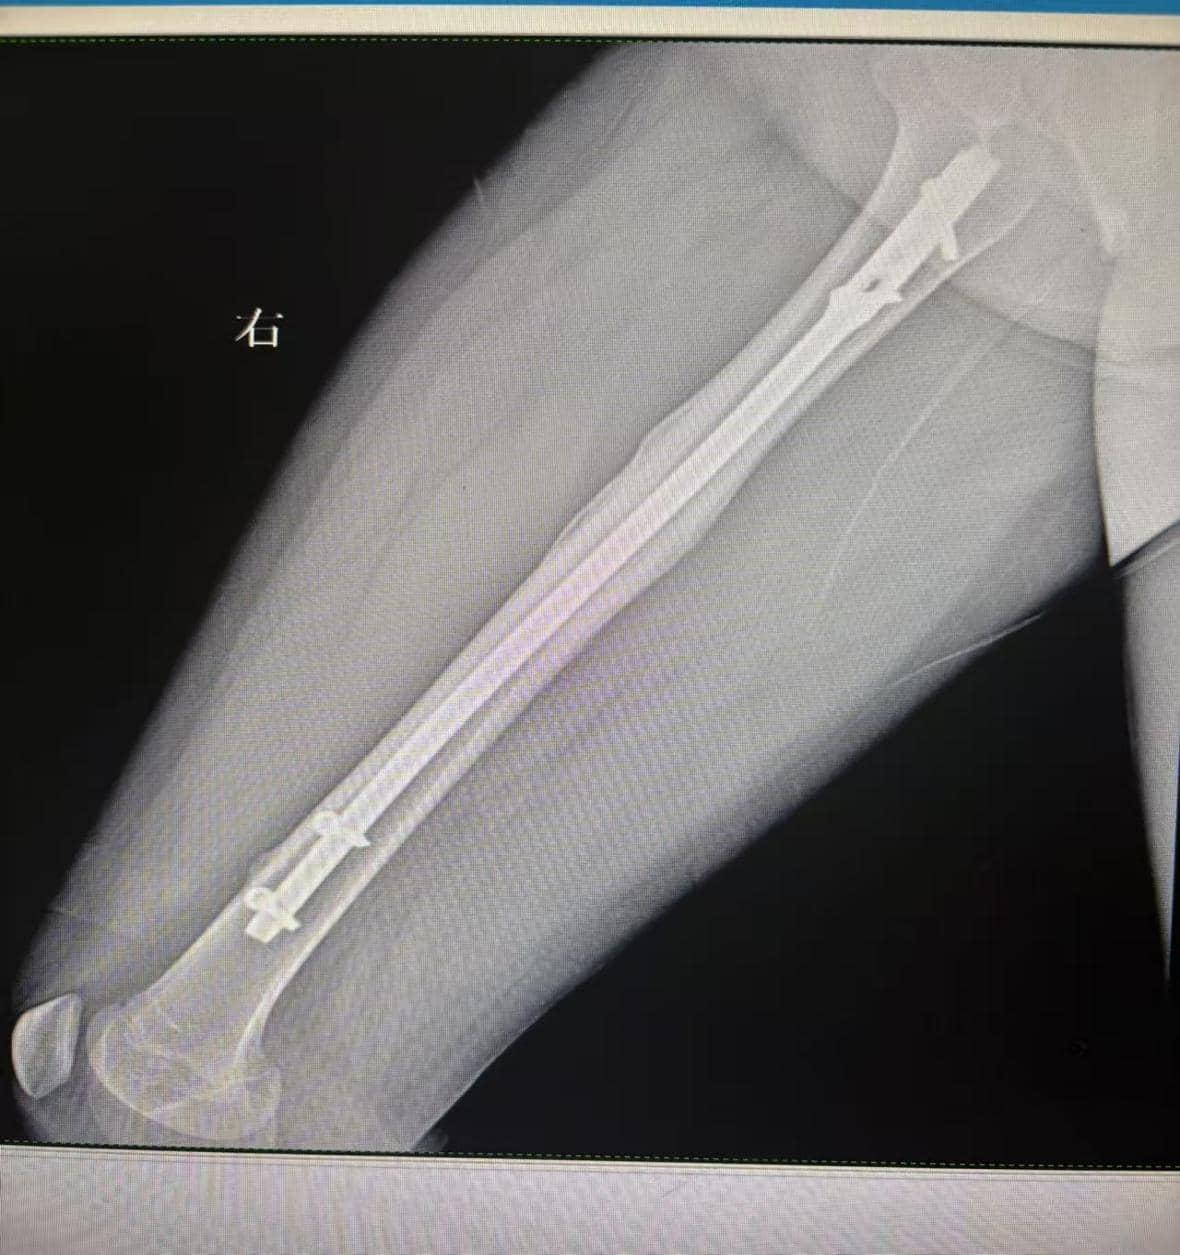

5岁的童童(化名)因玩耍时摔倒导致左侧大腿肿胀疼痛,诊断为儿童股骨干骨折。考虑到儿童骨骼愈合快但塑形能力强,团队采用闭合复位髓内钉固定术:无需切开皮肤暴露骨折端,仅通过2个不足1厘米的小切口,将合适规格的髓内钉经骨髓腔植入,实现骨折复位与固定。术后3天,童童即可在床上进行肢体活动,避免了传统手术长期卧床可能导致的肌肉萎缩。